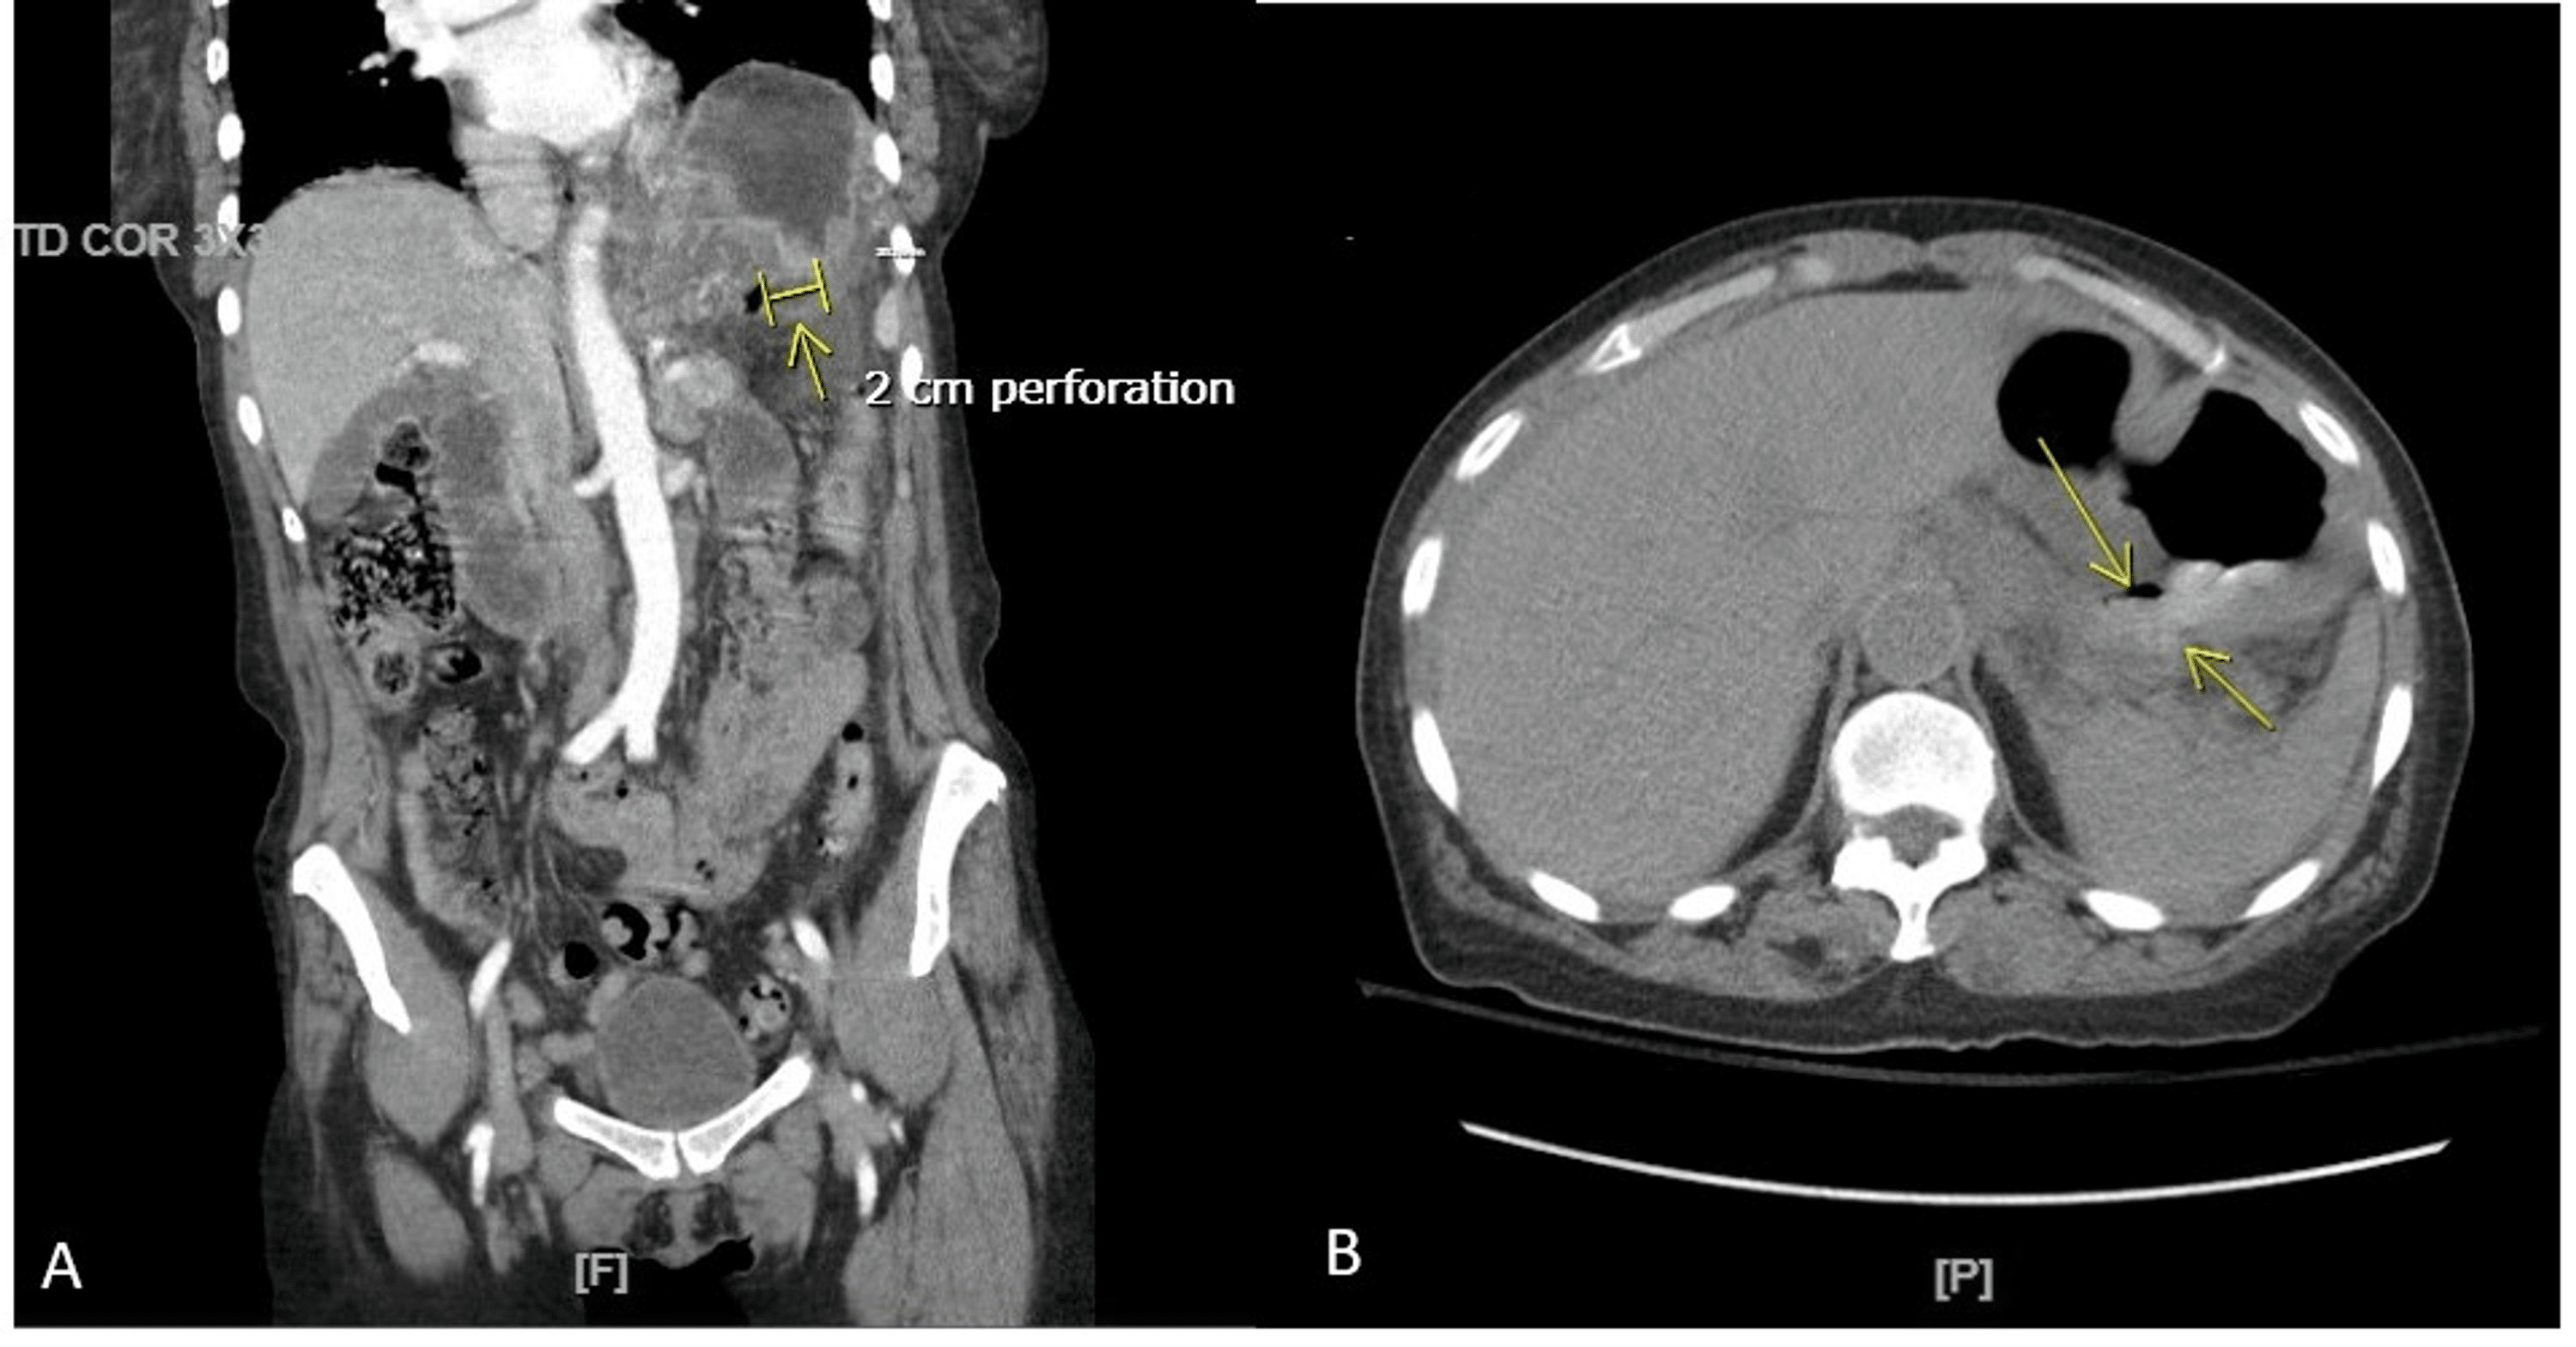

Perforated duodenal ulcer Image Ct Scan Ulcer Thickening and swelling of the bowel wall; However, this modality has a role in the detection of subphrenic and other collections that may occur. • multiplanar ct interpretation allows detecting deep ulcers and secondary signs of gastroduodenitis. In the acute setting ct is the modality of choice for assessing a patient with acute abdominal pain, and in some settings. Abdominal. Ct Scan Ulcer.